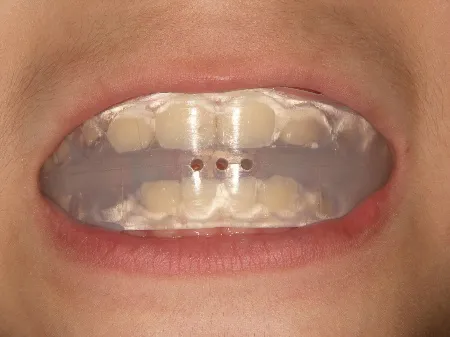

モノブロック装置(筋機能的咬合誘導装置)スタート

モノブロック装置*装置はイメージ